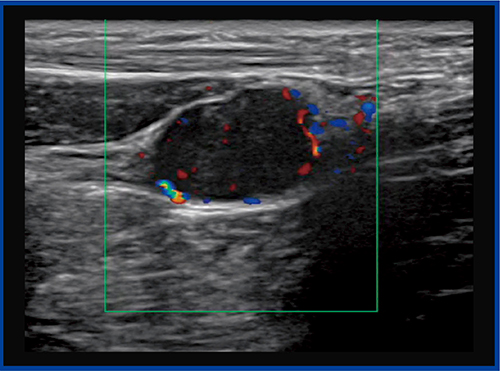

●症例2:第2趾MTP関節炎

症例2は,Bモードにて中足骨と基節骨の関節の腫れと,関節液の貯留が確認され,一部に初期の骨びらんが疑われた(図5)。カラードプラ(図6)では,滑膜には豊富な血流が見られるが,骨びらんが疑われる部位にはほとんど血流が認められなかった。一方,SMI(図7)では,骨びらんの周囲から骨の中に流入する血流がわずかに認められた。

本症例は,未確定ではあるがリウマチが疑われる。通常,リウマチの診断はカラードプラを用いて行われるが,カラードプラでは滑膜の血流状態だけを見ているため,SMIを加えることで,リウマチ発生初期から見られる骨びらんを早期に評価できるようになると期待される。

図5 症例2:第2趾MTP関節炎のBモード画像

図6 症例2のカラードプラ画像

滑膜には豊富な血流が見られるが,骨びらん周囲にはあまり血流が見られない。

図7 症例2のSMI画像

骨びらん周囲から骨の中に流入する血流をわずかに認める。